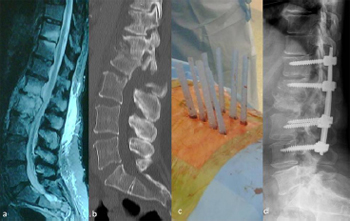

5.1.1. Illustrative patient 1

A 73-year-old male presented with neurogenic claudication and

mechanical lower back pain of 3 years' duration. Imaging revealed

severe canal stenosis at L4/5 due to spondylolisthesis, and facet joint/ligamentous hypertrophy. A midline incision and posterior

lumbar interbody fusion was performed. The midline incision was

closed and percutaneous screws inserted using the II technique.

Blood loss was 180 mL with discharge from hospital on day 4.

Fig. 10. Middle panel. Post-operative photograph of illustrative patient 1, a 73-

year-old male who presented with L4/5 degenerative spondylolisthesis with

neurogenic claudication. (a) Lateral image intensifier (II) radiograph showing Grade

I spondylolisthesis; (b) sagittal T2-weighted MRI showing severe canal stenosis; (c)

photograph at 8 weeks showing post-operative incision; (d) lateral II image

showing initial midline incision and posterior lumbar interbody fusion; (e) lateral II

percutaneous pedicle screw fixation pre-reduction; and (f) lateral II final radiograph

showing reduction of spondylolisthesis.